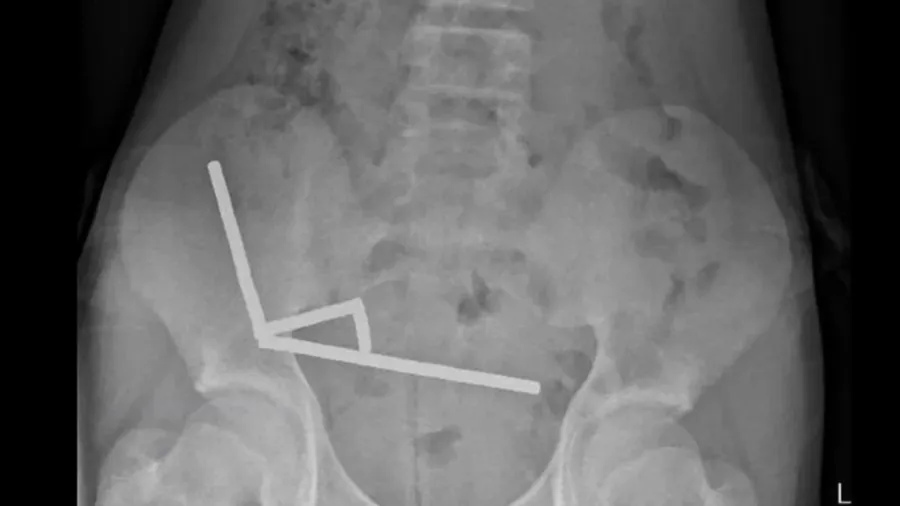

એક્સ-રેમાં તેના આંતરડાના જુદા જુદા ભાગોમાં ચુંબકની બનેલી ચાર સાંકળો ફસાયેલી જોવા મળી હતી, જે એકબીજાને ખેંચી રહી હતી અને નજીકના કોષોમાં લોહીના પ્રવાહને રોકી રહી હતી. ડોકટરોએ અહેવાલ આપ્યો કે, દબાણને કારણે નેક્રોસિસના ઘણા પેચ બની ગયા હતા, જેના માટે તાત્કાલિક સર્જરી કરવાની જરૂર પડી.